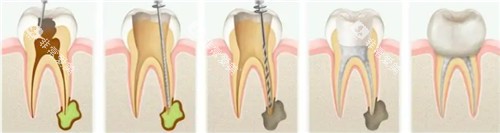

德恒口腔专注于口腔疾病的治疗和预防。

在牙周病治疗方面,德恒口腔有着独特的治疗方法。

医生们会根据患者的病情制定个性化的治疗方案,采用综合治疗的方法,包括洁治、刮治、药物治疗等,有效地控制牙周病的发展。

在牙齿美容方面,德恒口腔能够为患者提供牙齿贴面、冷光美白等多种美容项目,让患者拥有洁白亮丽的牙齿。